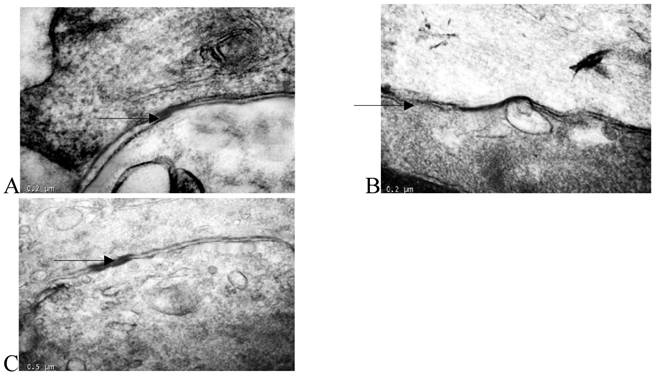

Transmission electron microscopy showed that there were many large-volume gap junction structures between proliferating smooth muscle cells, but few small-volume gap junction structures were observed between normal smooth muscle cells (Fig. 3).

Figure 3

Thin-section electron micrographs indicated gap junctions between smooth muscle cells in the rabbit iliac arteries of the normal group (panel A), high fat diet group (panel B), and high fat diet plus losartan group (panel C). In panel B, neointimal smooth muscle cells showed abundant and large gap junction when compared with normal group and losartan treated group. Bar=0.2 μm for panels A, B, C and D, × 65,000.